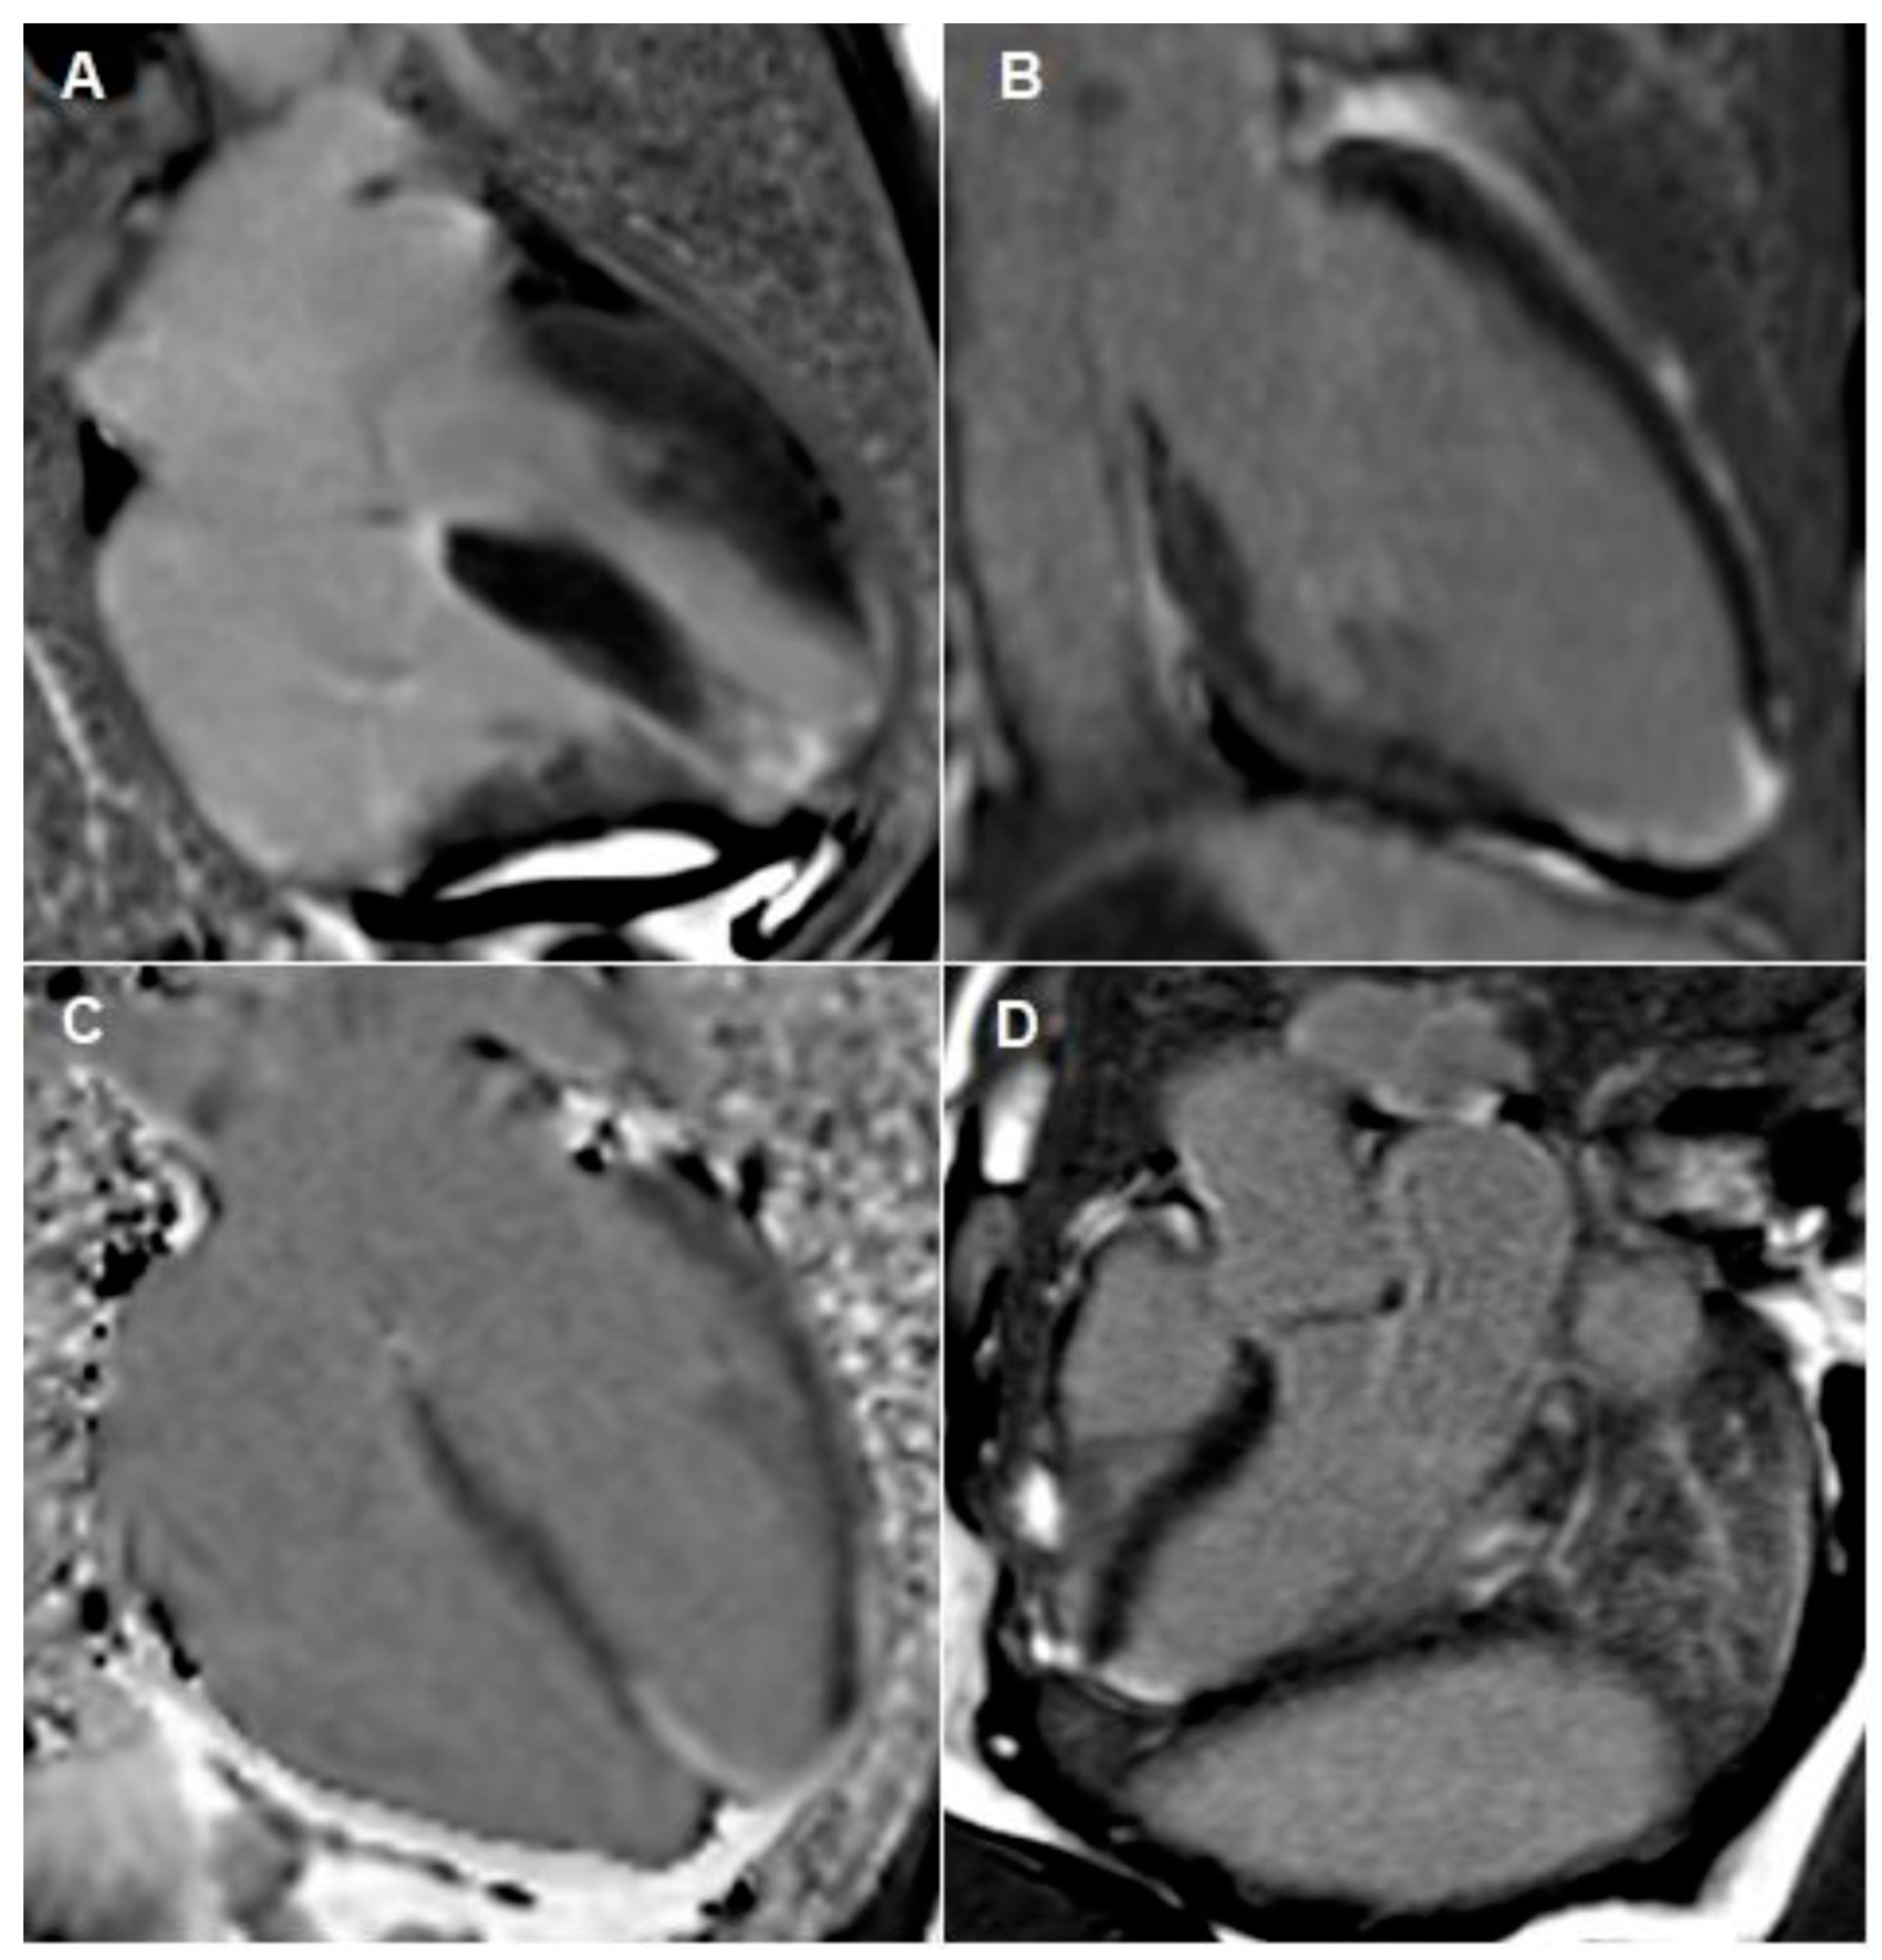

Figure 4.

Cardiac MRI images taken during both admissions. (A–C) outlines apical infarction. These images outline focal transmural late gadolinium enhancement in apical septum with sub-endocardial myocardial late gadolinium enhancement extending into the distal apical anterior, apical inferior and true apical segments. Image (D) outlines inferior-lateral infarction, which occurred during her second admission.

The formal echocardiogram confirmed similar findings to that carried out by the bedside, with further results found. Hypokinesia of the mid to apical inferior segments was found along with a bright myocardium. Grade 1 diastolic dysfunction was also noted. Moreover, a bright pericardium was noted with no evidence of pericardial effusion. Also, there was no obvious flow across the interatrial septal wall. Despite that, her transthoracic echocardiographic images could not exclude the possibility of a PFO. Whilst her D-dimer levels came back as normal, her 24 h ECG tape confirmed five episodes of atrial fibrillation (min heart rate 90, max heart rate 146), with each episode separated by short intervals of sinus rhythm (atrial fibrillation lasted for 4 h and 43 min in total). Furthermore, her cardiac MRI confirmed preserved global left ventricle systolic function with hypokinesia at the apex (Figure 4A–C). A small apical infarction was noted with one non-viable segment (out of a total of seventeen for the entire left ventricle). As such, her admission of acute apical myocardial infarction (MI) was thought to be caused by an embolic phenomenon, precipitated by either paroxysmal atrial fibrillation (pAF) or a possible PFO. In order to delineate the cause, a bubble echocardiogram was carried out (Figure 5), something which is considered as a useful investigative tool for diagnosing cardiac wall malformations [5]. Subsequently, a reasonably sized PFO was found, wherein moderate amounts of bubbles were seen crossing the intra-atrial septum during normal breathing and during Valsalva maneuver (Figure 5). She was therefore discharged on aspirin 75 mg once daily, bisoprolol 1.25 mg twice daily, edoxaban 30 mg once daily (later doubled to 60 mg once daily) lansoprazole 30 mg once daily, and ramipril 1.25 mg once nightly. She was also due for outpatient work-up for PFO closure at a tertiary Centre.

Despite that, two months later, she reattended the Accident and Emergency Unit with a second episode of chest pain. An ambulatory ECG outlined poor R wave progression and T wave inversion in the lateral leads (Figure 1B). Her troponin was again elevated from 173 as initial and on repeat (Table 1), 1017 to 532 to 375. Her vital signs were however unremarkable (heart sounds 1 and 2, heart rate 77, chest clear, no calf tenderness). Her chest X-ray was also unchanged (Figure 2B). A 24 h ECG tape found her to be in sinus rhythm throughout (mean 71 bpm). However, compared to her previous cardiac MRI, a repeated scan exemplified a new inferolateral full thickness MI (Figure 4D) with myocardial edema and microvascular obstruction of two affected segments (with clear RWMA). This is in addition to her previous mature full thickness apical septal MI (2 segments), and despite these developments, her systolic function remained preserved. A complete thrombophilia screen was not carried out.